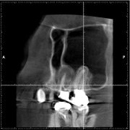

CTやレントゲンを使った徹底的な検査・診断・チェック

根管治療では、マイクロスコープや拡大鏡を使うことにより肉眼では見づらい根管をはっきり見ることができます。

しかし、複雑な歯の根の中を治療するには、それらだけでは万全ではありません。

当院では、CTやレントゲンを使って目に見えない部分の問題やポイントも見逃しません。

CTやレントゲンのデータは、治療前の徹底的な検査や診断に役立てるほか、治療後のチェックにも使用されます。

CT画像の例